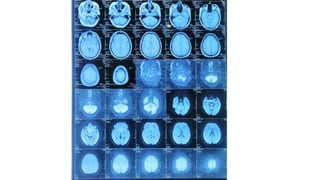

Radiological findings

• Multiplaner sagital ,coronal and axial images show a well defined ,midline, broad dural based,

lobulated T1WI iso , T2WI iso to slightly hyper and FlAIR hyperintense mass noted in suprasellar

Radiological findings • Multiplanersagital ,coronal and axial images show a well defined ,midline, broad dural based, lobulated T1WI iso , T2WI iso to slightly hyper and FlAIR hyperintense mass noted in suprasellar area having extension forwards along the planum sphenoidale and backwards along the dorsum sellae. • After IV contrast avidly homogenous enhancement of the lesion and adjacent linear dural enhancement over the clivus and planum sphenoidale representing dural tail are noted. • The lesion causing compression over the optic chiasma, pituitary gland and floor of 3rd ventricle, and encasing the supraclinoid ICA, ACA and MCA of both sides. • The mass effect is evidenced by obliteration of Suprasellar & interpeduncular cysterns and symmetrical indentation of underlying cerebral cortex. • No perilsional edema is noted • However lateral , 3rd and 4rth ventricles appear normal • Complementary CT cut was taken and showing iso to slightly hyperdense lesion. No calcification is noted. Bone CT shows bony hyperostosis at planum sphenoidale .Sellar size is within normal limit

Radiological diagnosis • Suprasellarmeningioma with planum sphenonale and dorsum sallar extension